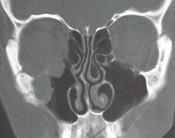

问题 女性,50岁,右鼻塞、脓涕3个月,CT、MRI检查如图所示,请选择正确的答案()

选项 A.右侧上颌窦黏液囊肿 B.右侧上颌窦粘膜下囊肿 C.右侧上颌窦积液 D.右侧上颌窦黏液腺瘤 E.右侧上颌窦腺样囊性癌

答案 E